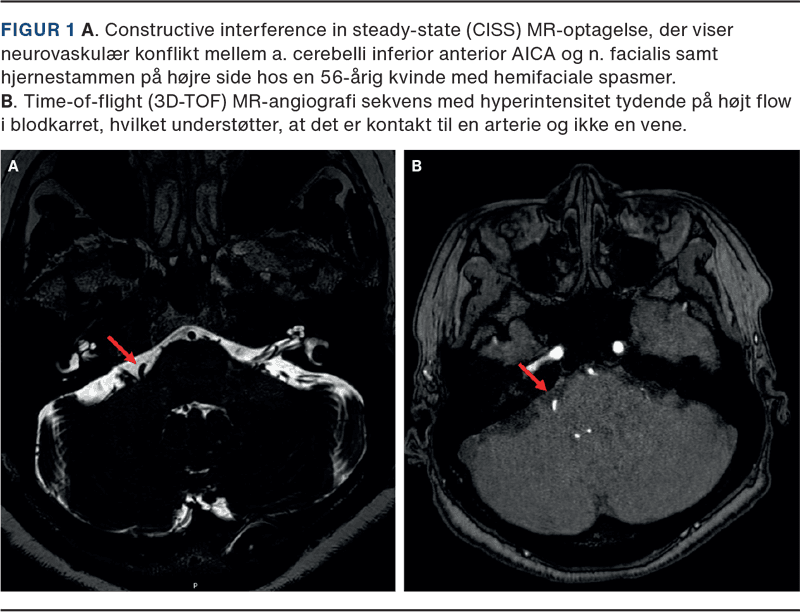

Påvisning af en eventuel strukturel årsag til symptomerne sker ved MR-skanning af hjernen og den relevante kranienerves forløb i de basale cisterner i fossa posterior. En 3 tesla 3D-T2-vægtet optagelse som constructive interference in steady-state (CISS) vil i de fleste tilfælde kunne påvise en eksisterende neurovaskulær konflikt, og 3D-time-of-flight (TOF)-MR-angiografi hjælper med at skelne mellem de relevante vener og arterier i området [1, 2]. Et eksempel på en MR-skanning med neurovaskulær konflikt mellem AICA og n. facialis hos en patient med højresidige hemifaciale spasmer fremgår af Figur 1.